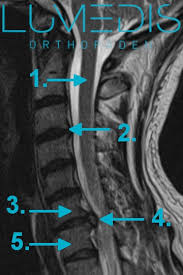

Hws Syndrom Schwindel Lumedis Wirbelsaulenspezialisten